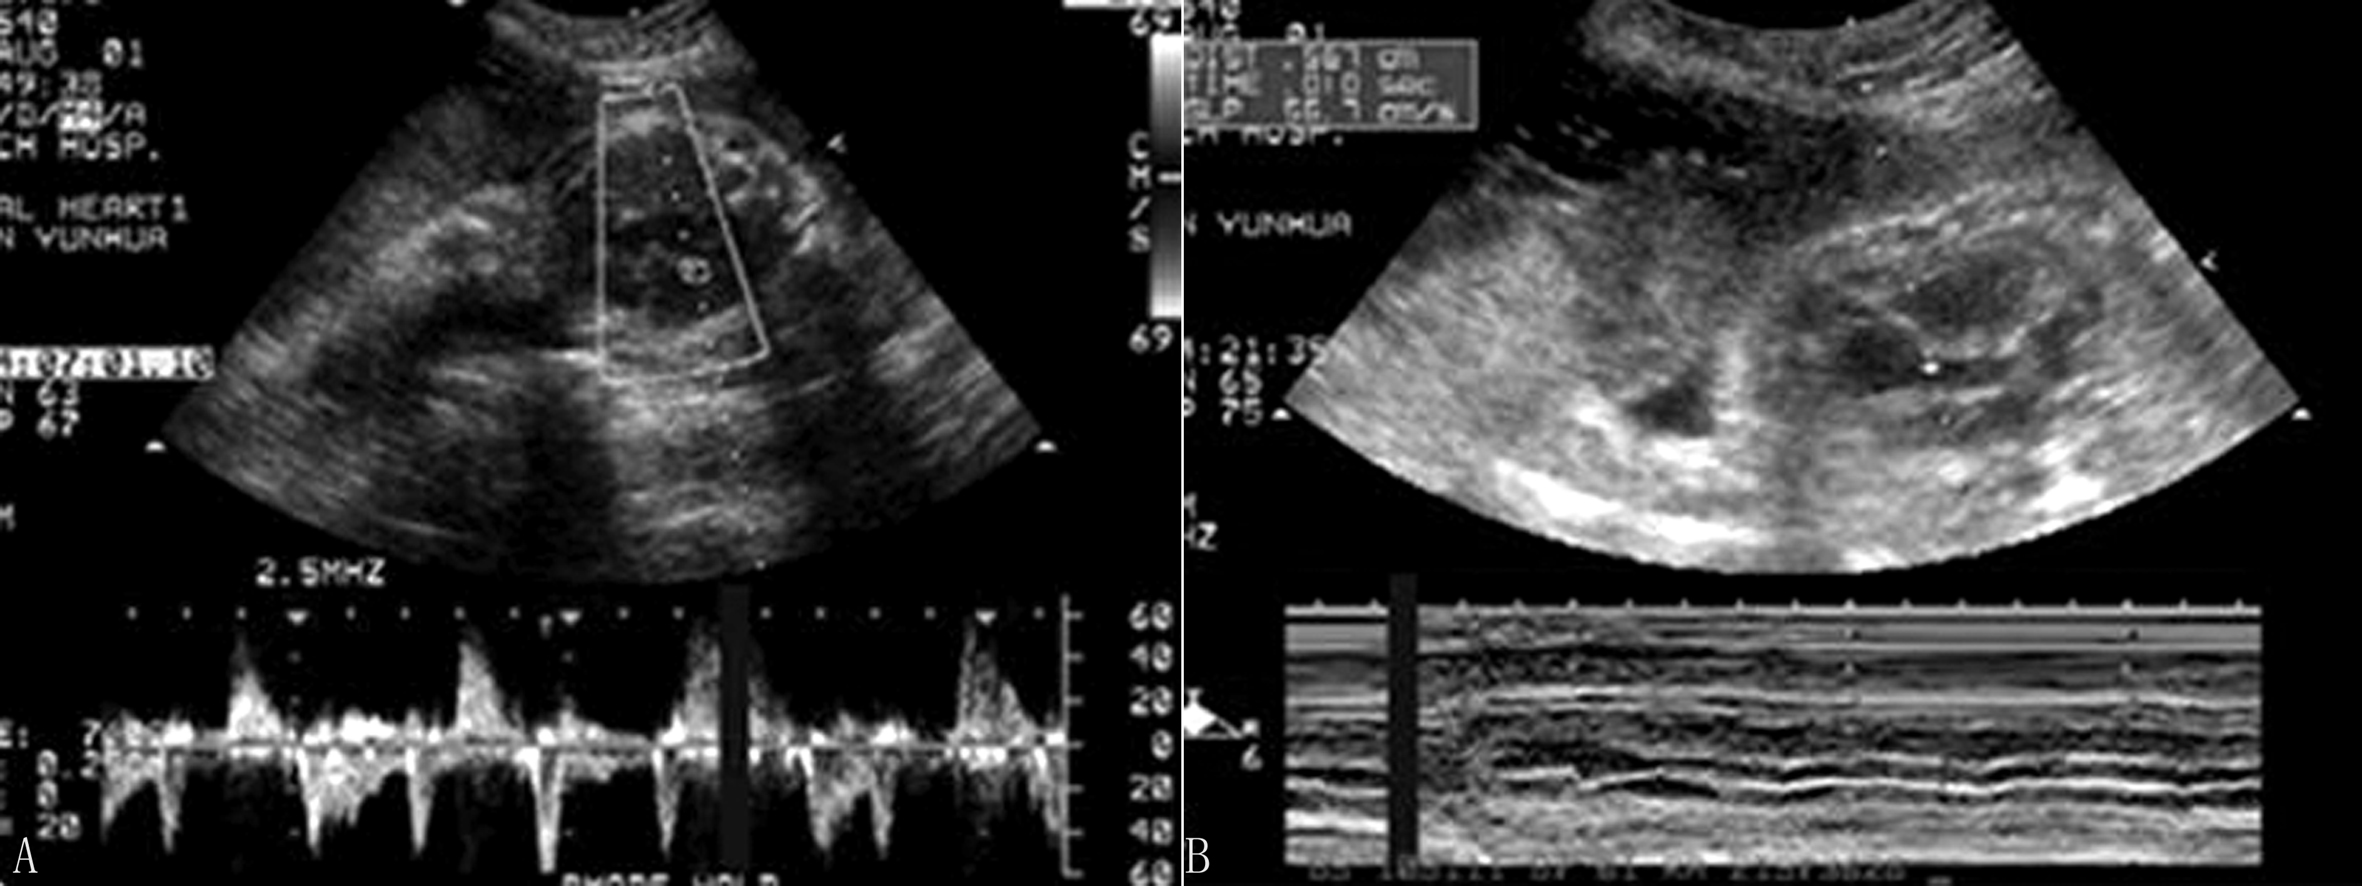

2.超声诊断要点 完全性房室传导阻滞心房收缩波与心室收缩波无关联,各有自己的节律。不完全性房室传导阻滞在多普勒血流时间流速曲线图上表现为:心室收缩波不是紧跟在心房收缩波后面,但与心房收缩波有关,如心室收缩波紧跟在心房收缩波后面应考虑心动过缓可能。M型超声由于振幅较低,有时难以判断,现多用脉冲多普勒时间流速曲线图进行分析,根据心房收缩波与心室收缩波的关系,得出推断结论(图4)。

图4 胎儿完全性房室传导阻滞